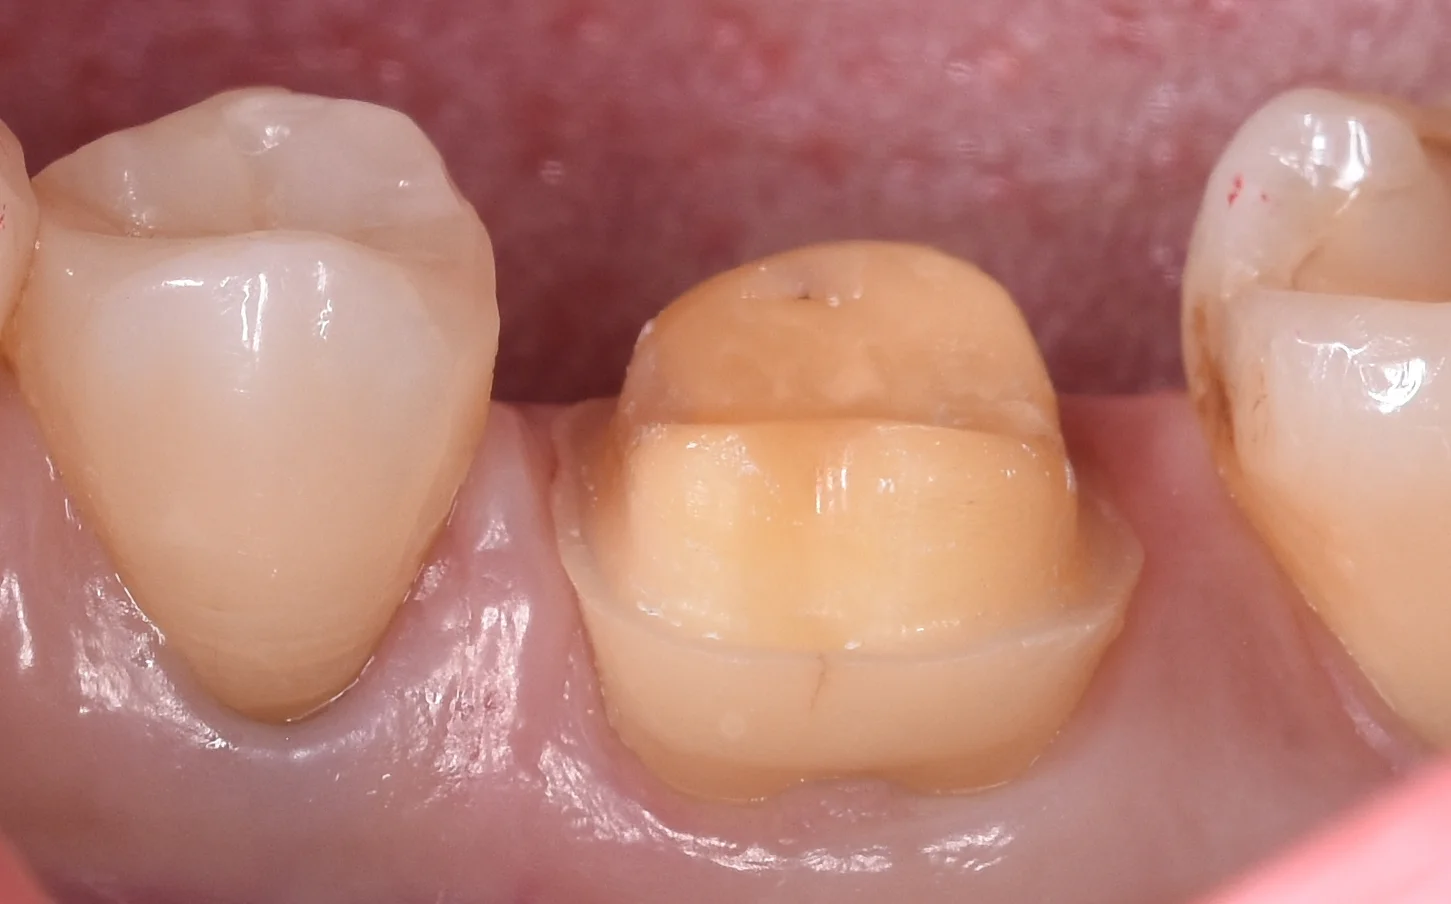

術前の状態からです。

術前というより形作りして型取りする直前の状態ですね。

基本的にセラミックは全周綺麗に厚みが取れるようにしておかないと噛む力を支えられずにセラミックが割れてしまいます。

そのため、こういう感じで全体的に大きく削る必要が出てきます。

今回は金属の詰め物を詰めた歯に亀裂が入ってしまい、その結果噛むと痛むという症状が出てしまっていました。

通常であれば歯の温存を考えるとこういうケースでは金属の方が有利なのですが、下の奥歯で口を開くと普通に見えてしまう場所だったため、セラミックを希望されました。

側面からの写真がこちらになります。

歯の亀裂部分を覆い隠せばいいだけだったので、審美性よりも歯の温存を優先して歯茎の下まで削り込まないようにしました。

側面にある亀裂に関してはここは問題ないと判断し、除去はしていないです。